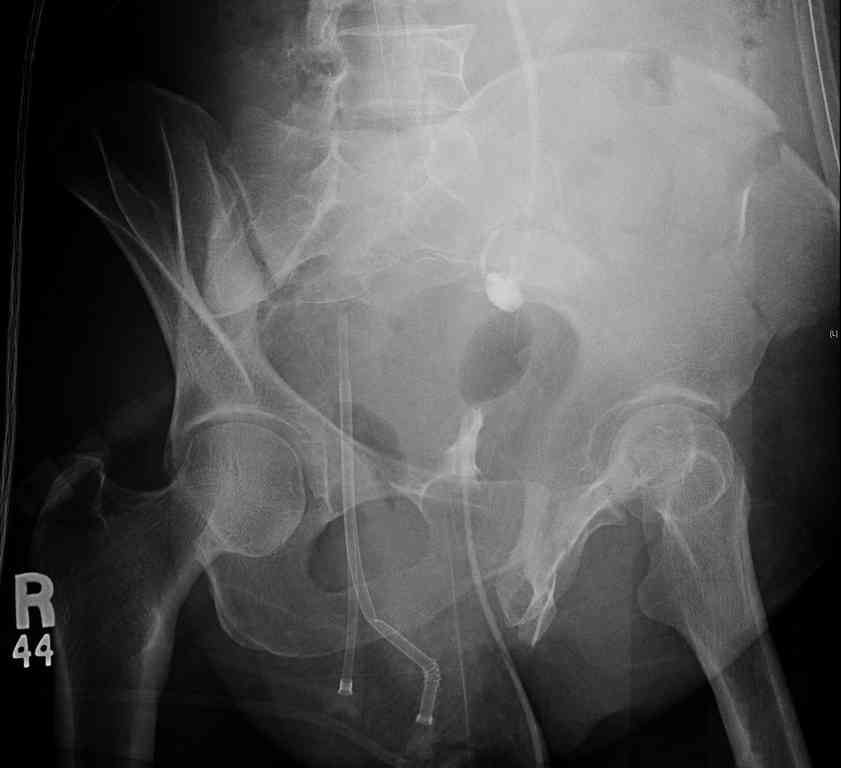

[Ortho] comminuted crescent fx

40 ish female ejected from car. Unstable, DPL negative, went to angio and had her pelvic bleeds embolized after many units of blood. GCS 6, floating elbow, clavicle, bothbones, etc.

My standard approach to  this pelvis would be posterior, reduce/lag/plate  thecrest, reduce/plate the caudal extent on the posterior crest and 1-2 lags back to front. In this case, the crest comminution seems to make plating all

the way to the ASIS useless, as the plate would be on free floating fragments. Would plating the posterior extent of the fracture to secure the

reduction at the SI joint and 2 screws back to front be sufficient fixation? Would anyone do a perc reduction and perc back to front screws, and would that be sufficient if the SI joint could be reduced (although I don't see how this could be accurately reduced closed). Would an ilioninguinal with a pelvic brim plate and posterior column screws be a better approach, although reducing the SI would be more indirect and less accurate?